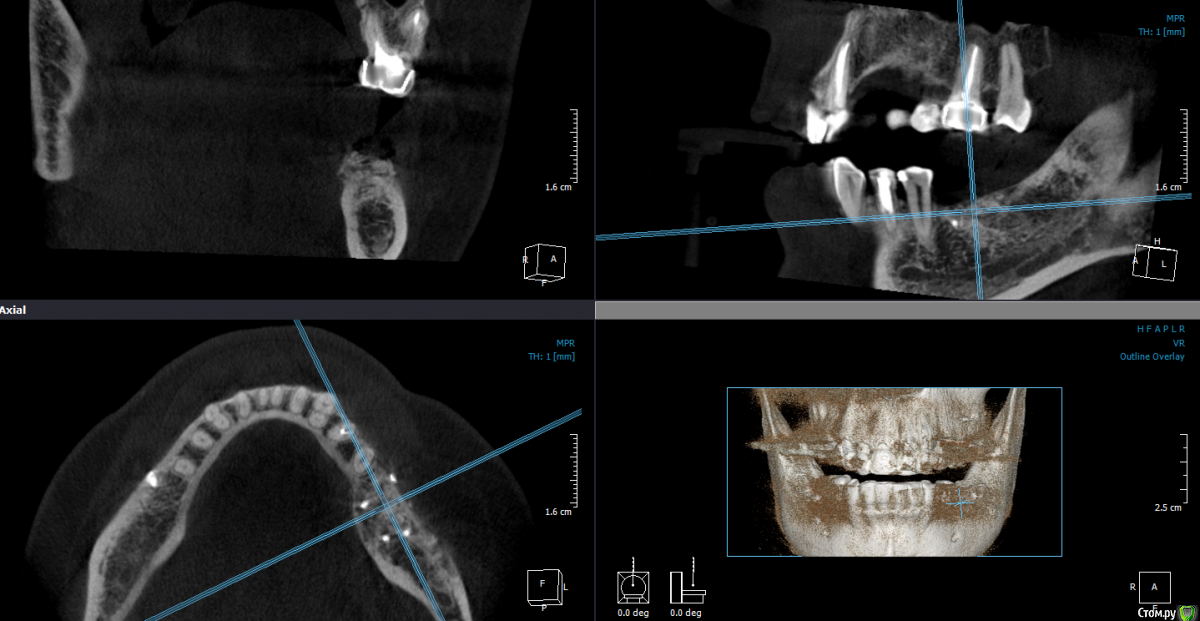

Mane Опубликовано 22 декабря, 2014 Поделиться Опубликовано 22 декабря, 2014 в целом хорошо. но нет деталей где я смогу понять что качественно отработали: 1) кт срезы до и после с замерами чтоб было понятно на сколько нарастили 2)кт срезы с установленными имплантами чтоб было понятно какие болты удалось установить и стало чтоб всем понятно для чего наращивали - ведь вы растили в высоту и в ширину. 3) фото на этапе установленных имплантов - соотношение платформы импланта и уровня кости - заглубили или нет - если да то насколько. Ориентировались ли на будущий зенит зуба. мне понравилось. но чуйка что есть гиперлечение - думаю можно было болты и костную пластику совместить. Растить по высоте я скорее всего бы не стал. 1 Ссылка на комментарий

SDC Опубликовано 22 декабря, 2014 Поделиться Опубликовано 22 декабря, 2014 Через 5 месяцев...Мне не понравилось просветление в 3 квадранте. Крутили КТ? Что это? Ссылка на комментарий

Dantist55 Опубликовано 22 декабря, 2014 Автор Поделиться Опубликовано 22 декабря, 2014 в целом хорошо. но нет деталей где я смогу понять что качественно отработали: 1) кт срезы до и после с замерами чтоб было понятно на сколько нарастили 2)кт срезы с установленными имплантами чтоб было понятно какие болты удалось установить и стало чтоб всем понятно для чего наращивали - ведь вы растили в высоту и в ширину. 3) фото на этапе установленных имплантов - соотношение платформы импланта и уровня кости - заглубили или нет - если да то насколько. Ориентировались ли на будущий зенит зуба. мне понравилось. но чуйка что есть гиперлечение - думаю можно было болты и костную пластику совместить. Растить по высоте я скорее всего бы не стал.КТ посмотрю позже на работе - я в отпуске.По высоте добавляли чтобы зубы не получились большими.Импланты не заглублял, т.к. у XIVE полированная фаска.Насчет гиперлечения может Вы и правы. Эту работу я сделал сразу после приезда от Кури. 2 Ссылка на комментарий

Dantist55 Опубликовано 22 декабря, 2014 Автор Поделиться Опубликовано 22 декабря, 2014 Мне не понравилось просветление в 3 квадранте. Крутили КТ? Что это?Перед имплантацией крутил-все было норм. Ссылка на комментарий